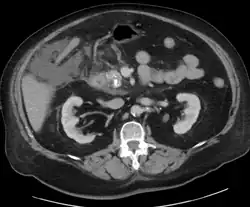

Acute exudative pancreatitis on CT scan

A contrast-enhanced CT scan is usually performed more than 48 hours after the onset of pain to evaluate for pancreatic necrosis and extrapancreatic fluid as well as predict the severity of the disease. CT scanning earlier can be falsely reassuring.[34]